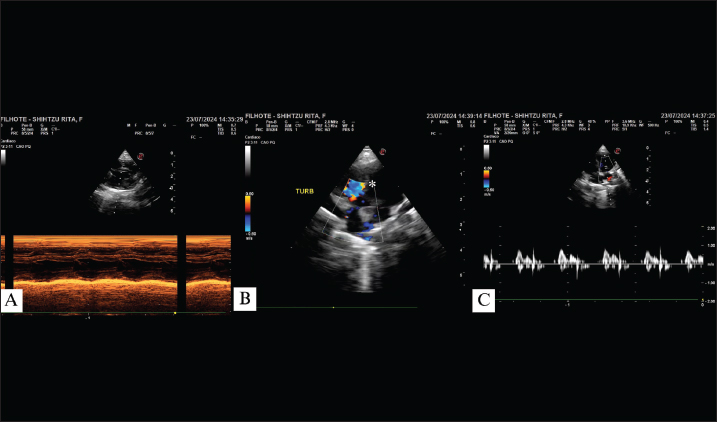

A rescued, female Shih Tzu puppy, approximately 45–50 days of age, was taken for pediatric evaluation along with two of her brothers following the sudden death of another puppy from the same litter. The physical assessment revealed a grade 3 out of 6 heart murmur, although the other parameters were within normal ranges. The patient was the smallest puppy in the litter and present body condition score of 3/9. Subsequently, the patient was referred to an echocardiographic evaluation, which revealed a left-to-right VSD (Fig. 1). Because of the absence of cardiac remodeling or clinical signs, follow-up was indicated, and another echocardiogram associated with a microbubble test was performed to confirm the diagnosis. Upon returning after 15 days, the development of herniation in the diaphragmatic region, pectus carinatum, and posterior myofibrillar hypoplasia was noted.

Fig. 1. Echocardiogram of a 45-day-old patient showing right ventricular overload with preserved systolic function in M-mode (A); turbulent flow in the perimembranous ventricular region (*) due to ventricular septal defect (B); E wave surpassing A wave with preserved IVRT values (C). TURB: turbulent flow.